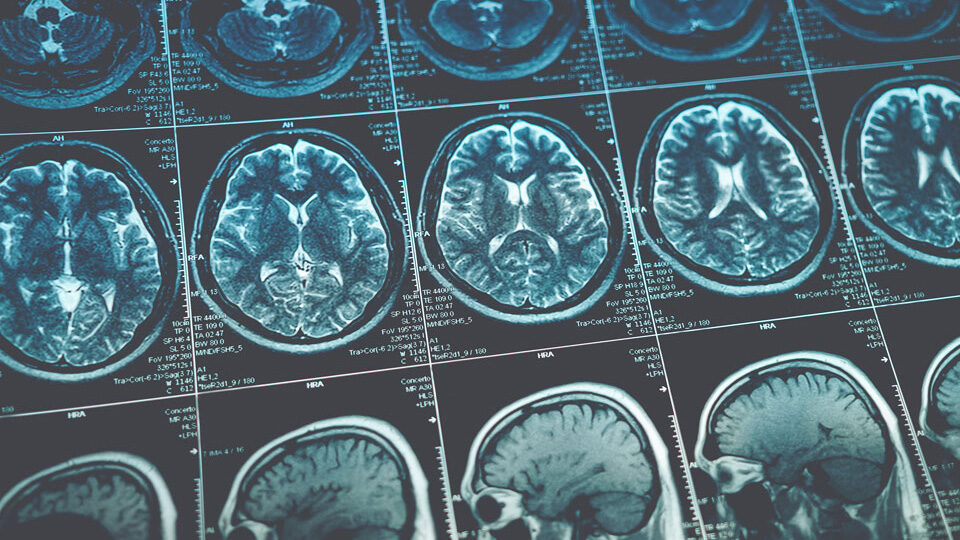

Подозрение на опухолевое образование – это показание к МРТ и КТ головного мозга с контрастом. Может быть назначена ангиография сосудов мозга, ПЭТ и другие дополняющие обследования. В некоторых случаях помочь в определении типа рака может биопсия, но сделать ее можно не во всех случаях.